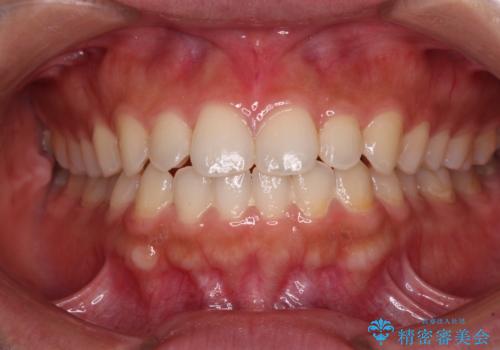

- 上顎前歯の叢生を気にして来院された患者様です。

下顎前歯や上下奥歯の咬み合わせには殆ど問題がないため、上顎前歯のみを矯正する治療を提案しました。

ワイヤー装置でもインビザラインでも可能でしたが、前歯のみをきれいに排列するのであればインビザラインの方が仕上がりが良いので、インビザライン・ライトにて治療を行うこととしました。